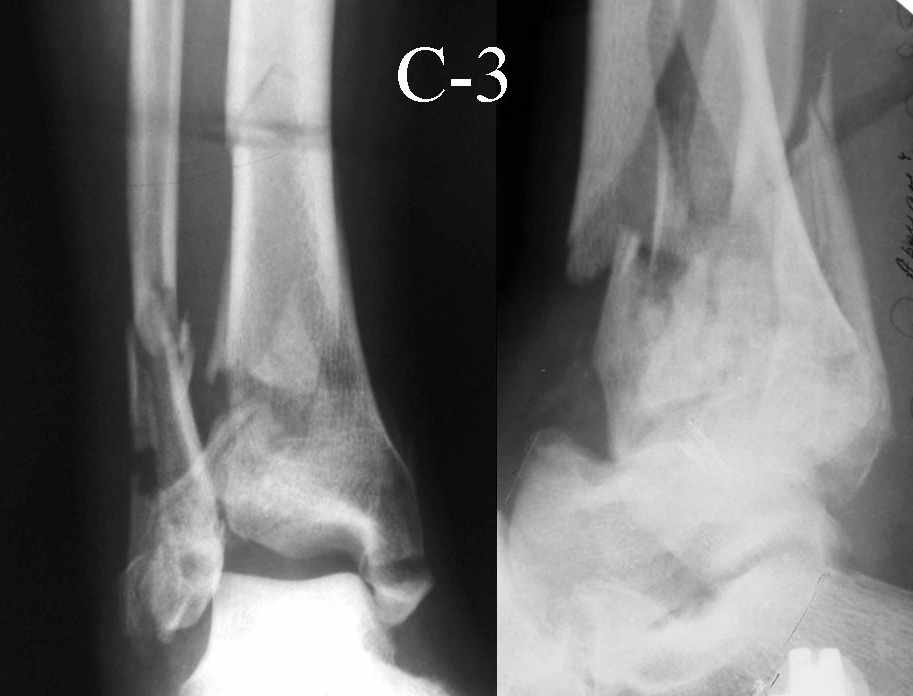

На рентгенограммах типичный перелом пилона по типу С-3. есть опыт до 100 открытых опреаций у нас в клинике. 20 примерно в год. Принцип один -все внутрисуставные переломы нуждаются в открытой репозиции и внутренней стабильной фиксации. При поступлении КТ не надо, так как получается только нагромождение костей. Истинной картины нет. Главное восстановить длину малоберцовой кости - это ключ к успеху. При поступлении меньше всего надо думать о сосудистых расстройствах, т.к. сама операция и репозиция даже сначала частичная даёт улучшение сосудитых нарушений. Причём очень быстро. Операция в 2этапа. При поступлении доступ позади наружной лодыжки, причём обязательно. После этого репозиция малоберцовой кости и фиксация пластиной 1/3 трубки под винт 3,5. Дренаж и любой аппарат наружной фиксации. Затем после спадения отёка на 5-7-10 день аппрат снимается и дугообразный разрез спереди от медиальной лодыжки 10-12 см. Главной чтобы расстояние между 1 и вторым разрезом было не меньше 7-8 см. Тогда не будет некрозов лоскутов. Таранная кость используется как матрица на неё укладываются отломки и фиксируются пицами. Ренг-контроль. Отломки лежат все отдельно, но ничего не высыпется. При переломах С-3 всегда нужна костная пластика (из крыла). Фиксация пластиной лист клевера простой или LCP. Гипс не нужен. Дренаж до 48 часов. Операция длится 3-4 часа обязательно без жгута. Посылаю примерно такой же случай.

Это типичный перелом пилона, который надп лечить только открыто.Извини те что опоздал к обсуждению, но даже если вы уже оперировали больного по Илизарову это даже лучше.Посылаю картинки.